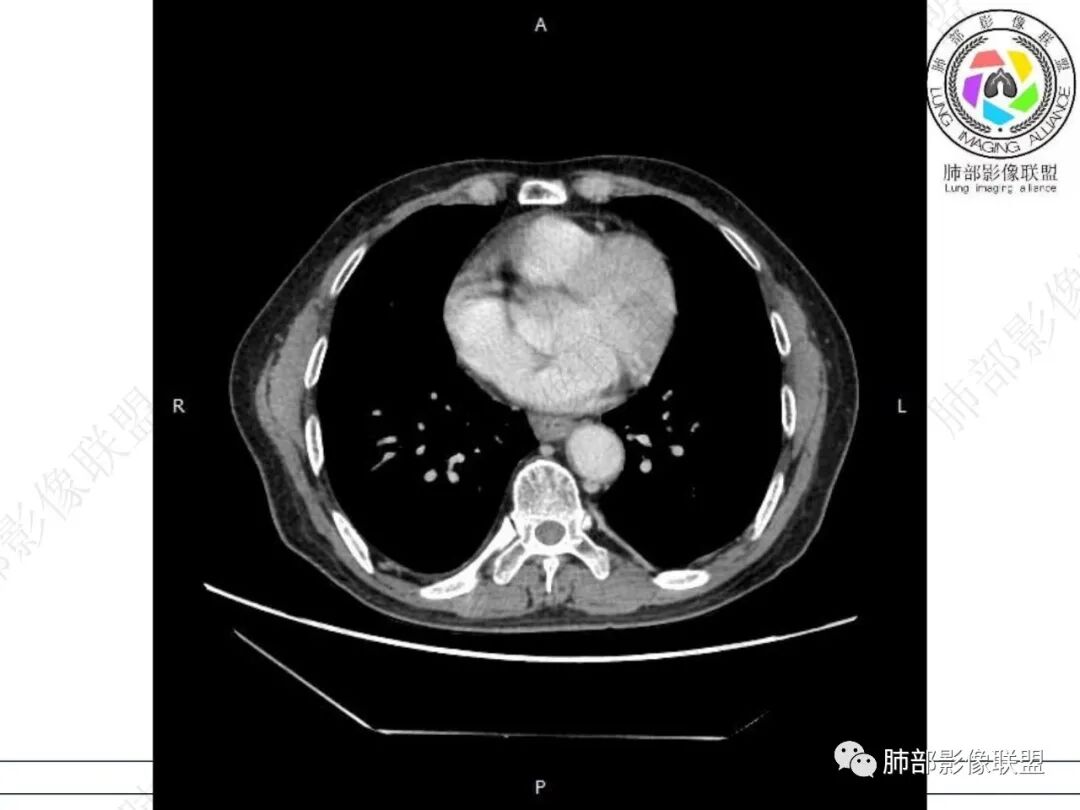

右肺下叶沿肺叶肺段分布斑片、条片状影,以下叶背段为显,边缘模糊,内可见支气管走行,局部支气管管壁增厚,右侧胸腔少量积液。纵隔隆突下可见不均匀软组织密度影,与周围结构分界不清,内见气体密度影,与食管及相邻右肺支气管之间未显示通道。邻近食管下段壁明显不规则增厚,增强后食管管壁明显不均匀强化,可见线样强化的连续完整粘膜影。

右肺下叶片影,气道相关,符合感染性病变。纵隔隆突下软组织密度影,异常气体影,长病程,起病缓慢,提示存在气管或食管瘘。食管镜未见明显新生物形成,临床未提供进食或饮水呛咳临床表现,综合分析应该考虑支气管瘘的形成。

对比患者3月份的CT图,原隆突下存在增大钙化淋巴结,现在出现气体影,且钙化显示不清,应想到淋巴结结核破溃成瘘可能性。